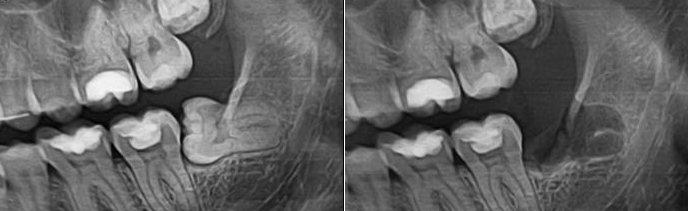

Резекция верхушки корня зуба: фото до и после

Современная резекция верхушки корня зуба предусматривает тщательное перепломбирование и проведение на уровне проекции кончика корня ампутации поврежденной верхушки (апекса). Главным преимуществом резекции верхушки зуба является сохранение целостности зубной дуги, так как операция предусматривает исключительно отсечение пораженной части корня. Это и позволяет сохранить сам зуб. Вот почему данная процедура называется зубосохраняющей.

В клинике «Дока-Дент» резекция корня зуба выполняется следующим образом. Изначально через разрез на десне стоматолог удаляет кисту или гранулему, после чего отсекается зараженный участок корня. Затем в образовавшуюся рану вводятся специальные препараты, которые призваны ускорить регенерирующие процессы и как можно быстрее восстановить костную ткань. Далее разрез на десне зашивают. И когда она полностью заживет, зуб при желании можно закрыть коронкой. Все манипуляции во время резекции проводятся с использованием местной анестезии.

Грамотно выполненная резекция верхушки корня зуба защищает его от инфекции. Благодаря резекции зуб может прослужить еще не один десяток лет, если пациент будет соблюдать рекомендации своего врача.